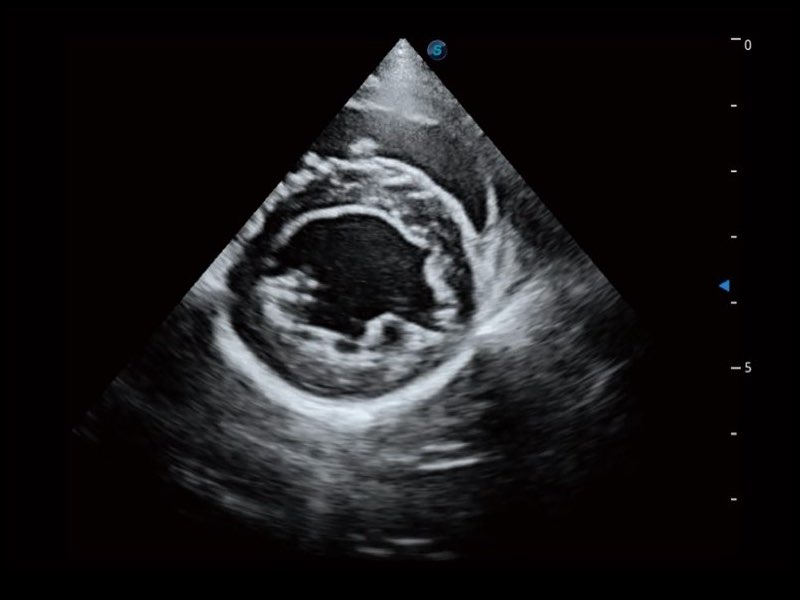

Przy pracach nad aparatem ProPet 60 uwzględniono najważniejsze preferencje i potrzeby weterynarzy, oferując finalnie przystępne cenowo i odpowiednio wyważone połączenie znakomitej precyzji klinicznej, zwiększonej wydajności i przemyślanego przebiegu pracy, niezastąpione w codziennej praktyce weterynaryjnej. Dzięki dostępowi do pełnej gamy głowic HD rozwiązanie to spełnia wszystkie potrzeby w zakresie obrazowania, umożliwiając wykonywanie badań jamy brzusznej, małych narządów, ortopedycznych, badań podczas rozrodu, a nawet badań serca i klatki piersiowej, a to wszystko przy doskonałym stosunku jakości do ceny.